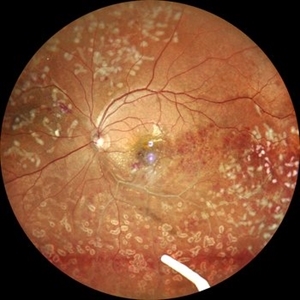

Wet age related macular degeneration Wet age related macular degenerationJan 28 2024 by Anjana Mirajkar, MS Ophthalmology Fundus photograph of an 70 year old male with sub retinal bleed and exudation as well as scarring in case of wet age related macular degeneration. Photographer: Dr. Anjana Mirajkar -Retina Foundation, Ahmedabad Imaging device: Mirante-Nidek Condition/keywords: choroidal neovascular membrane (CNVM), wet age-related macular degeneration (wet AMD)